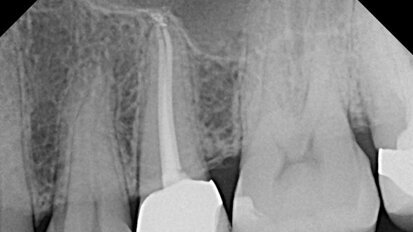

The patient pictured in Figure 1 was referred because the first clinician could not locate the canal(s). The patient had pain when chewing on #13 and mild ...